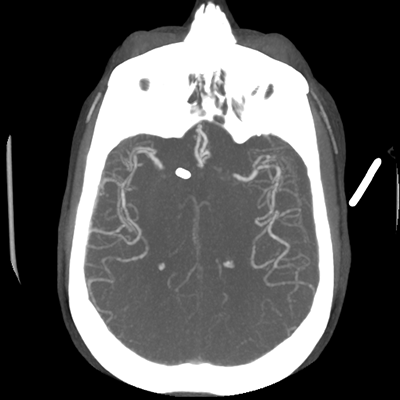

CTA head (MIP)

Starting with the non-contrast head CT, we can appreciate that there's actually not much residual subarachnoid blood at all; it's essentially all resorbed already (and cleared through the EVD). The ventricular caliber is stable. With the CTA head (for convenience's sake, the MIPs were shown), it's subtle, but we can see that the PCAs on each side are not as smooth and regular. The right MCA, starting at the bifurcation, also becomes narrower. This is [radiographic] vasospasm. Now, looking at the CT perfusion-- specifically, the Tmax (MTT) map that were selected-- there's clearly some abnormality within the bilateral cerebellar hemispheres and occipital lobes. Not a lot, but it's there. Delving further into this map, we can appreciate that the areas of abnormality are mainly green, signifying that these areas have Tmax > 6 seconds. This is the threshold that is specific, not sensitive, for vasospasm.

Putting this all together, we have thus identified radiographic vasospasm with the vessel imaging, with perfusion abnormalities that are concordant with it. Does the area of vasospasm and hypoperfusion correlate with the patient's clinical exam?

Yes! It does. The patient had a decline in level of consciousness with diffuse loss of motor function. This does correlate to the basilar territory. (Alternatively, bilateral MCA vasospasm could also be responsible, reminding us that a decline in consciousness could technically be focal/multifocal.) Thus, we can say that this patient does have clinical vasospasm. Whether this will develop into irreversible DCI remains to be seen; at least, the non-contrast head CT and the other portions of the CT perfusion (not shown) currently don't [yet] suggest infarction.